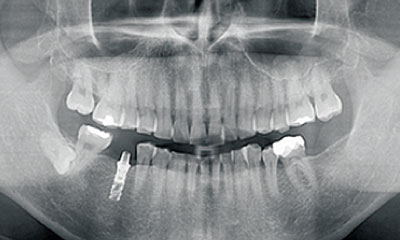

顎全体の骨量や口腔の状態を把握するために、CTを用いて詳細な検査を行います。

データを収集した後、シミュレーションソフトを活用して、インプラント埋入を支援するサージカルガイドを作成します。